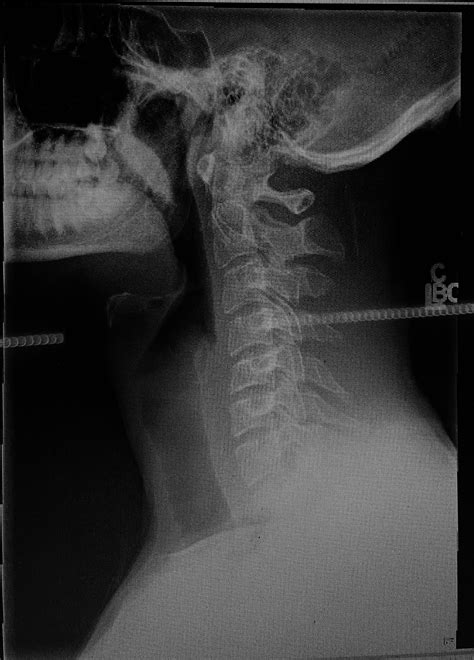

Imaging Tests

Imaging tests, such as X-rays, MRI, or CT scans, can help identify structural abnormalities or inflammation in the psoas muscle and surrounding areas. These tests can provide valuable information for diagnosing the underlying cause of psoas making leg numb.